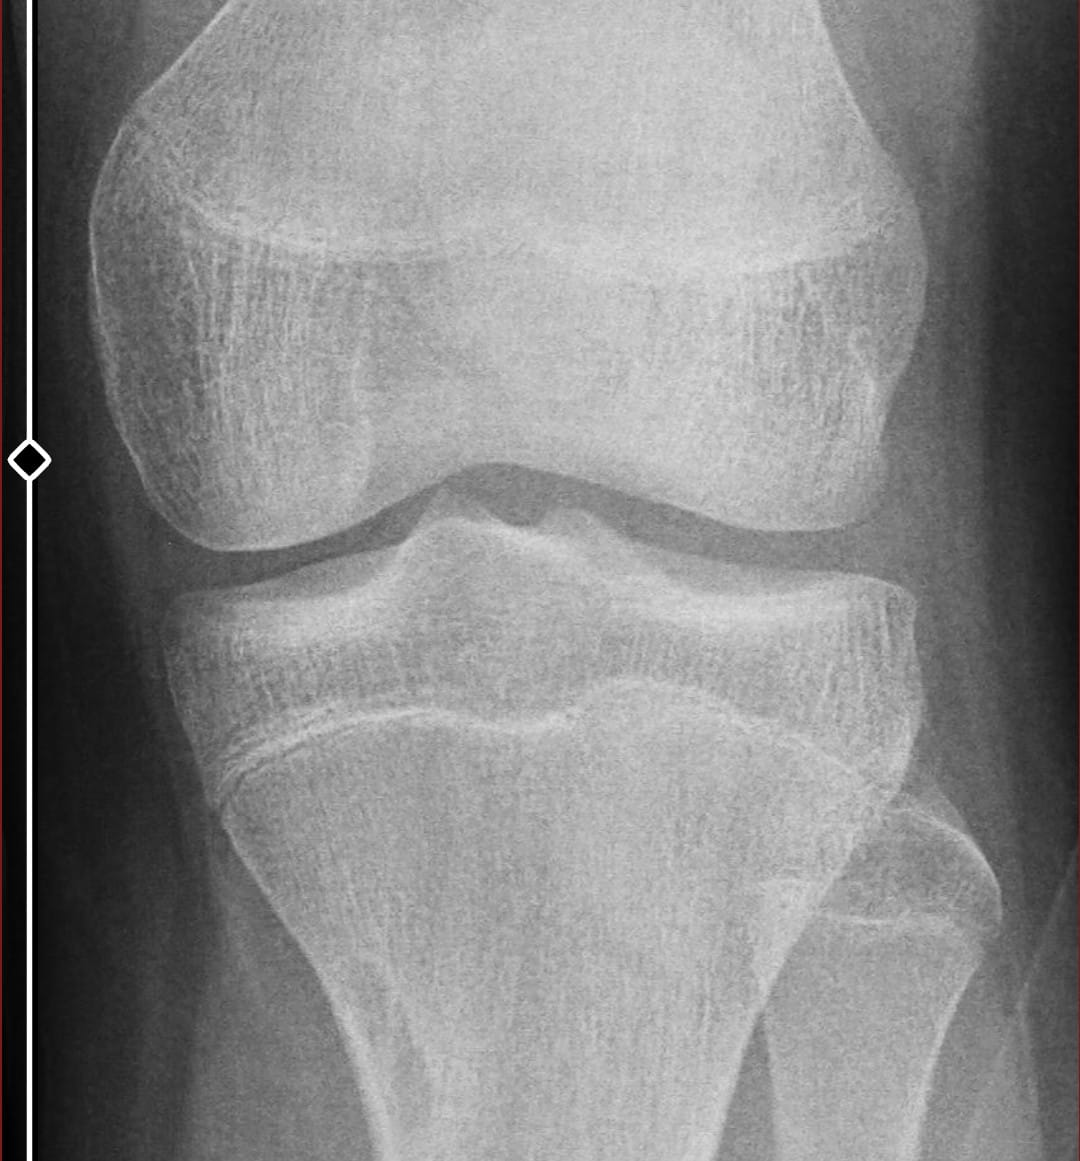

here is my knee x-ray

so can i grow an inch? idk i still look like a child. im tanner 4. my dad is 180 my mom is 170 and im 177

In this image, the growth plates (epiphyseal plates or physes) at the knee appear closed or fused

but how is that possible? i grew 3 centimeters in last 6 months im the shortest person in my whole family (including my cousins, uncles etc.)

and my plates were wide open 6 months ago and i controlled my e2. it seems impossible